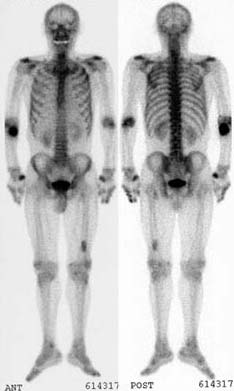

- Age/Sex: 66M

- Chief Complaint:椉壓巿捝偍傛傃峠挭

- 偁傞昦堾偵擖堾拞偺姵幰偵婲偙偭偨偱偒偛偲偱偡(偙偺強尒偑尨場偱擖堾偵側偭偨傢偗偱偼偁傝傑偣傫乯丅

- 側偤偙傫側強尒偵側偭偨偺偐丠峫偊偰梸偟偄偲偺弌戣幰偐傜偺僐儊儞僩偱偡丅

- Images:

- Bone scan

|

Whole-body

magnify magnify

|

Left lateral view

|

偁側偨偺恌抐偼 What

is your first impression?

What

is your first impression?

top